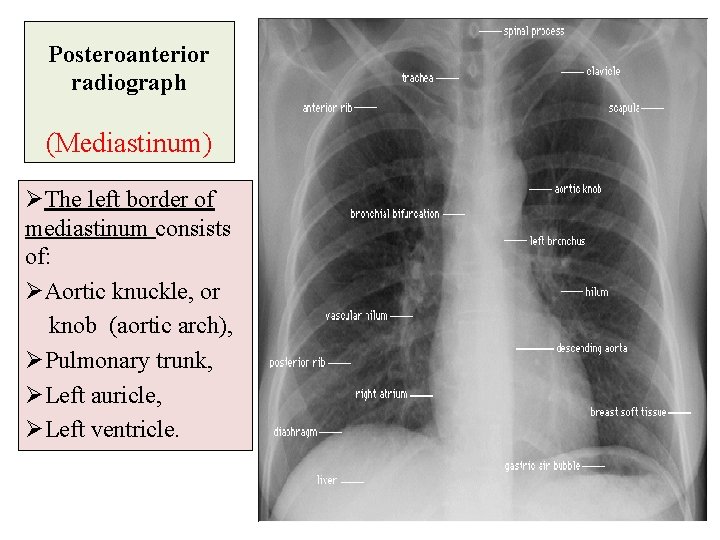

Posteroanterior radiograph (Mediastinum) ØThe left border of mediastinum consists of: ØAortic knuckle, or knob (aortic arch), ØPulmonary trunk, ØLeft auricle, ØLeft ventricle.

Posteroanterior radiograph (Mediastinum) ØThe transverse diameter of the heart should not exceed half the width of thoracic cage. ØOn deep inspiration, when the diaphragm descends, the vertical length of the heart increases and the transverse diameter is narrowed.